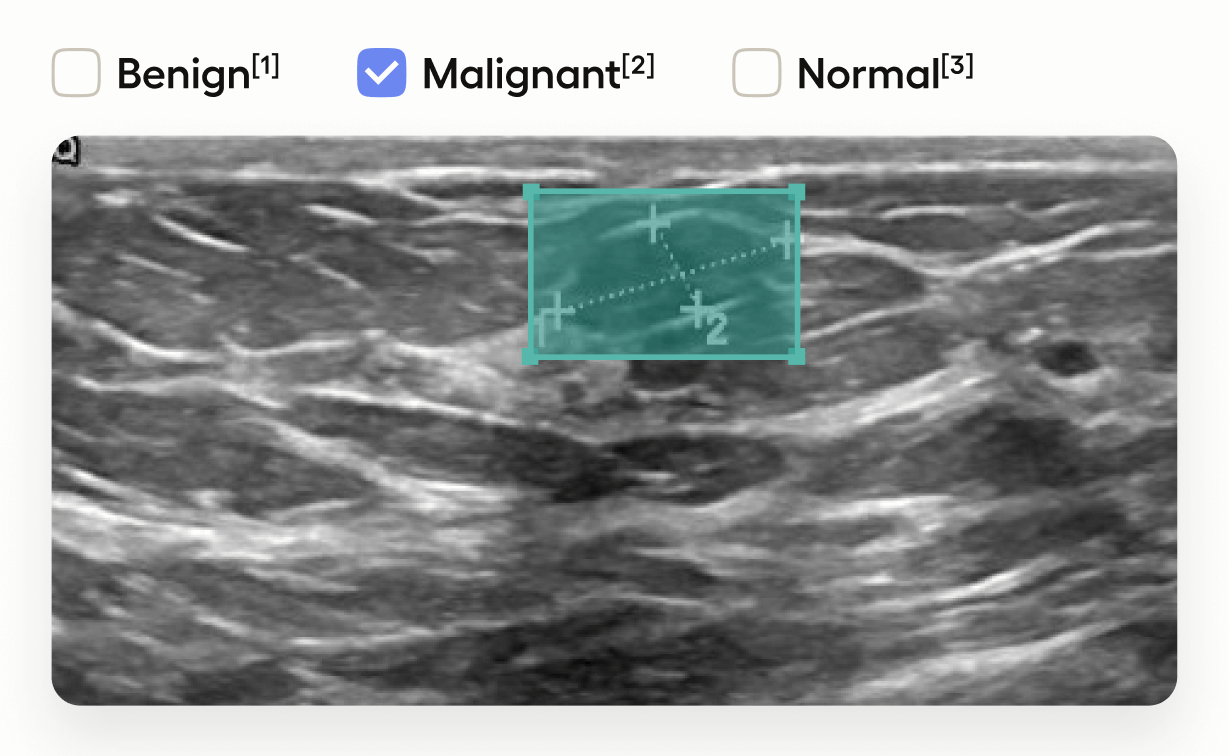

Medical Image Classification and Segmentation

Image Classification, object detection